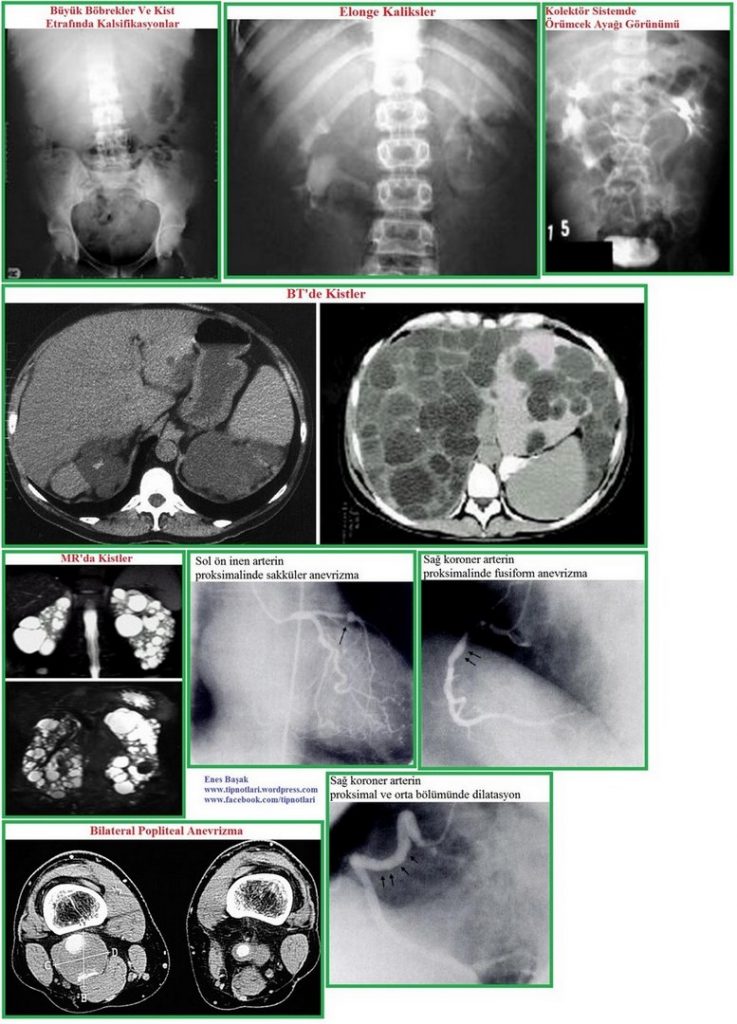

Tanı: Pozitif aile hikayesi önemlidir. Radyolojik incelemeler: 1-Ultrasonografi: aile hikayesi pozitif olan bir kişide ultrasonografik tanı kriterleri; <30 yaşta ünilateral veya bilateral 2 kist olması, 30-59 yaşta bilateral 2’şer kist olması, >60 yaşta bilateral 4’er kist olması. 2-Bilgisayarlı tomografi. 3-Magnetik rezonans görüntüleme. Gen bağlantı analizi.

Görüntüleme yöntemleri: Direkt grafi, intravenöz ürografi, ultrasonografi, bilgisayarlı tomografi, manyetik rezonans, anjiografi, nükleer yöntemler, retrograt piyelografi, intravenöz piyelografi, ekskretuvar ürografi.

Ultrasonografi tanı kriterleri: Riskli hastalarda; <30 yaşta her böbrekte bir kist olması, 30-59 yaşta her böbrekte iki kist olması, >60 yaşta her böbrekte dört kist olması.

Progresyon takibi: ultrasonografi ile; adolesan grupta beş yılda bir, 40 yaşından sonra üç yılda bir, 50 yaşından sonra iki yılda bir yapılır. Bilgisayarlı tomografi, ultrasonografi, manyetik rezonans takipte kullanılabilir.